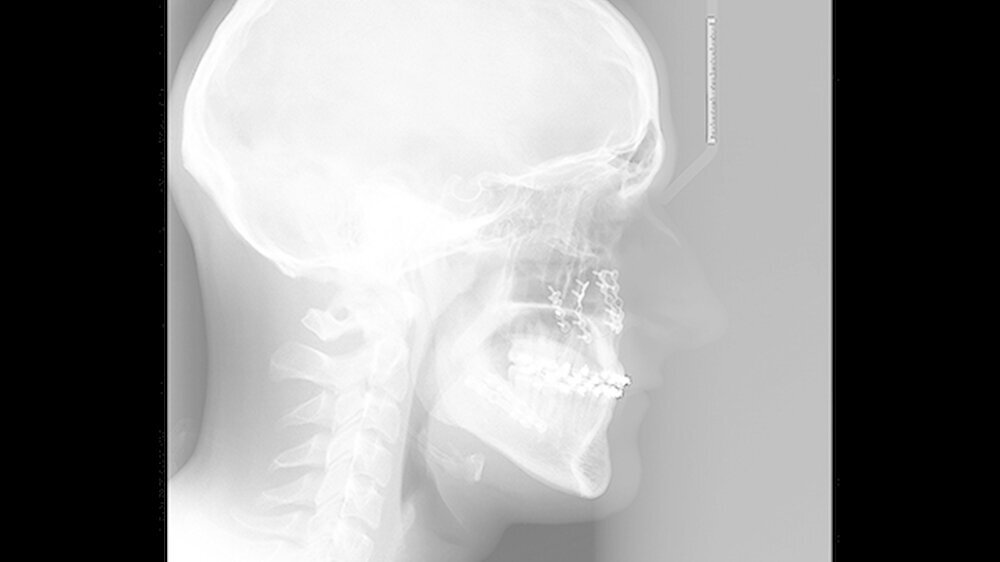

Die Abbildungen 1 und 2 zeigen die klinische Situation bei Erstvorstellung: Der Unterkiefer ist zu prominent. Der Oberkiefer und das Mittelgesicht liegen zurück. In der Front liegt ein umgekehrter Überbiss vor. Der Unterkiefer steht vor dem Oberkiefer. Das erschwert das Abbeißen und Kauen der Nahrung. Die Scans (siehe Abbildungen) dokumentieren, wie aufwendig die virtuelle Operationsplanung erfolgen musste.